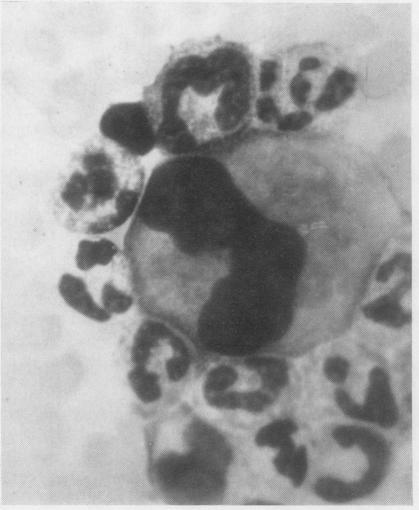

White-cell concentrates were made by a dextran sedimentation technique from the blood of 140 cases of malignant disease and 60 controls. The slides were searched for tumour cells and for other unusual cells with which they might be confused. Several million white cells were scanned in the slides from each case. Acceptable tumour cells were identified in the blood of seven patients, none of whom survived for more than a few months. These cells are illustrated, as well as various other cell types which may have been confused with malignant cells in the past. It is concluded that the cytology of white cell concentrates should be further explored before statistics about the occurrence of circulating tumour cells are accepted.

采用葡聚糖沉降技术从140例恶性疾病患者及60例对照者的血液中制备白细胞浓缩物。在玻片上查找肿瘤细胞以及可能与之混淆的其他异常细胞。对每个病例的玻片扫描数百万个白细胞。在7名患者的血液中鉴定出了可接受的肿瘤细胞,其中无一例存活超过几个月。文中展示了这些细胞以及过去可能与恶性细胞混淆的各种其他细胞类型。得出的结论是,在接受关于循环肿瘤细胞发生率的统计数据之前,应进一步探索白细胞浓缩物的细胞学。